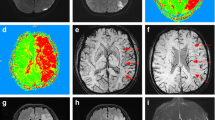

Ionic edema in contrast to cytotoxic edema means increase in water content and swelling of severely ischemic tissue (Fig. 2). In vitro measurements of X-ray attenuation and T1 and T2 relaxation in gelatin gels and eggs showed a linear relationship between CT attenuation and specific gravity/water content of the gel (r = 0.992; p < 0.0001) and no effect on X-ray attenuation by egg hardening with water content kept constant. A 1% increase in gel water content was associated with a decrease in X-ray attenuation of 2.6 Hounsfield units (HU). The relationship between T1 and T2 relaxation and gel water content was linear as well. A 6% increase in gel water content resulted in a 19% increase in T2 signal intensity in contrast to a 25% change in CT attenuation in the same specimens [40]. Moreover, cooking egg white while keeping water content stable considerably shortened T1 and T2 relaxation and impaired MR signal intensity showing the impact of bulk water transfer into bound water on MR signal intensity and demonstrating the complexity of MR signal intensity. Computed tomography can measure and follow ionic edema following MCA occlusion in the experimental animal [41,42,43]. Ischemic brain tissue water content increased steadily within 6 h of MCA occlusion from 77.9 to 79.3%, whereas X-ray attenuation declined from 75.6 to 71.7 HU meaning that a 1% increase in hemispheric tissue water content caused an attenuation decrease of 1.8 HU (linear correlation r = 0.55, p < 0.0001) [41]. In a reperfusion experiment, CT attenuation remained stable after initial decline after 1 h of MCA occlusion, but further decreased with reperfusion after 2, 3, and 4 h of occlusion [42]. Occlusion of the MCA in non-human primates decreased CBF below 10 ml/100 g × min for 4 to 6 h that was associated with an attenuation decrease of 4–5 HU [43]. A linear relationship between ischemic CBF and decrease in CT attenuation was also observed in ischemic stroke patients within 4.5 h of symptom onset [44].

Development of malignant infarction. a CT within 6 h of stroke onset. Subtle hypoattenuation of the total frontal lobe, insular cortex, temporal lobe, caudate, and lentiform nucleus (territories of middle and anterior cerebral arteries). b 12 h later: well-demarcated MCA and ACA infarction with effacement of sulci, but no mass effect. c At 24 h: mass effect with shift of midline structures and herniation of the right medial temporal lobe

Based on these experimental and clinical observations, it is evident that CT can detect and even quantify ionic brain edema and, thus, the volume of ischemic brain tissue that is irreversibly injured. This evidence was strongly supported by the prospective expert CT reading in the European Cooperative Acute Stroke Study II (ECASS II), a randomized controlled trial on the effect of alteplase in 786 ischemic stroke patients [45]. In this study, experienced neuroradiologists from three European countries assessed areas of CT hypoattenuation within 6 h of ischemic stroke onset blinded to follow-up CTs at 22–96 h and 2–36 days that served as reference standard for the measurement of diagnostic accuracy [46]. Six hundred seventy-nine patients had infarctions on follow-up CT. The positive predictive values for these infarctions were 98 and 95% for the alteplase and placebo-treated patients. The experts detected CT hypoattenuation in 433 out of 679 patients (64%) on baseline CT compared to 271 patients (40%) identified by the study sites. The authors incorrectly calculated CT sensitivity for “early infarct signs” from these numbers neglecting that follow-up imaging is an inappropriate reference for the assessment of baseline CT sensitivity, because ionic edema has possibly not yet developed within the first 6 h of stroke with focal brain ischemia below the CBF threshold for neuronal function impairment, but above the threshold for irreversible injury. Nevertheless, the local investigators at ECASS 2 study sites missed CT hypoattenuation in 162 patients adjudicated positive by expert neuroradiologists demonstrating that non-experts can miss subtle gray matter hypoattenuation caused by early stages of ionic edema, e.g., an increase in tissue water content of less than 1%. Furthermore, low-contrast resolution due to wide window settings impairs the recognition of early ionic edema with subtle hypoattenuation. Window and level settings on CT should provide a clear differentiation of gray and white matter allowing substantial inter-observer agreement [47, 48]. Post-processing of CT images with special software can further enhance gray-white matter contrast and increase CT sensitivity for ionic edema [49, 50].